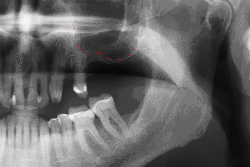

Biomechanické úvahy

Dlouhodobý úspěch implantátů je částečně dán silami, které musí unést. Jelikož implantáty nemají parodontální vaz, není při kousání cítit tlak, takže vytvářené síly jsou vyšší. Aby se to vyrovnalo, musí umístění implantátů rovnoměrně rozložit síly na celou protézu, kterou podporují.[25]:s.15-39 Koncentrované síly mohou vést ke zlomenině můstku, komponent implantátu nebo ke ztrátě kosti přiléhající k implantátu.[26] Konečné umístění implantátů vychází jak z biologických (typ kosti, vitální struktury, zdraví), tak z mechanických faktorů. Implantáty umístěné do silnější a pevnější kosti, jaká se nachází v přední části dolní čelisti, mají nižší míru selhání než implantáty umístěné do kosti s nižší hustotou, například do zadní části horní čelisti. Lidé, kteří skřípou zuby, také zvyšují sílu působící na implantáty a zvyšují pravděpodobnost jejich selhání.[12]:s.201-208

Pokud je potřeba přesnější plán nad rámec klinického úsudku, zhotoví zubní lékař před operací akrylové vodítko (tzv. stent), které slouží jako vodítko pro optimální umístění implantátu. Stále častěji se zubní lékaři rozhodují pro výpočetní tomografii čelistí a případných stávajících zubních náhrad a poté plánují operaci v CAD/CAM softwaru. Stent pak lze vyrobit pomocí stereolitografie po počítačovém naplánování z výpočetní tomografie. Použití tomografie ve složitých případech také pomáhá chirurgovi identifikovat a vyhnout se životně důležitým strukturám, jako je dolní alveolární nerv a sinus.[28][29]:s.1199